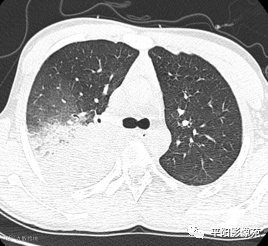

入院CT:

影像特征:X线片右肺中上野片状高密度影,下缘以叶间裂为界,上缘及外侧缘模糊;CT位于右肺上叶后段,呈片状实变影,内见支气管影,边缘模糊。

影像诊断:右肺上叶大叶性肺炎。